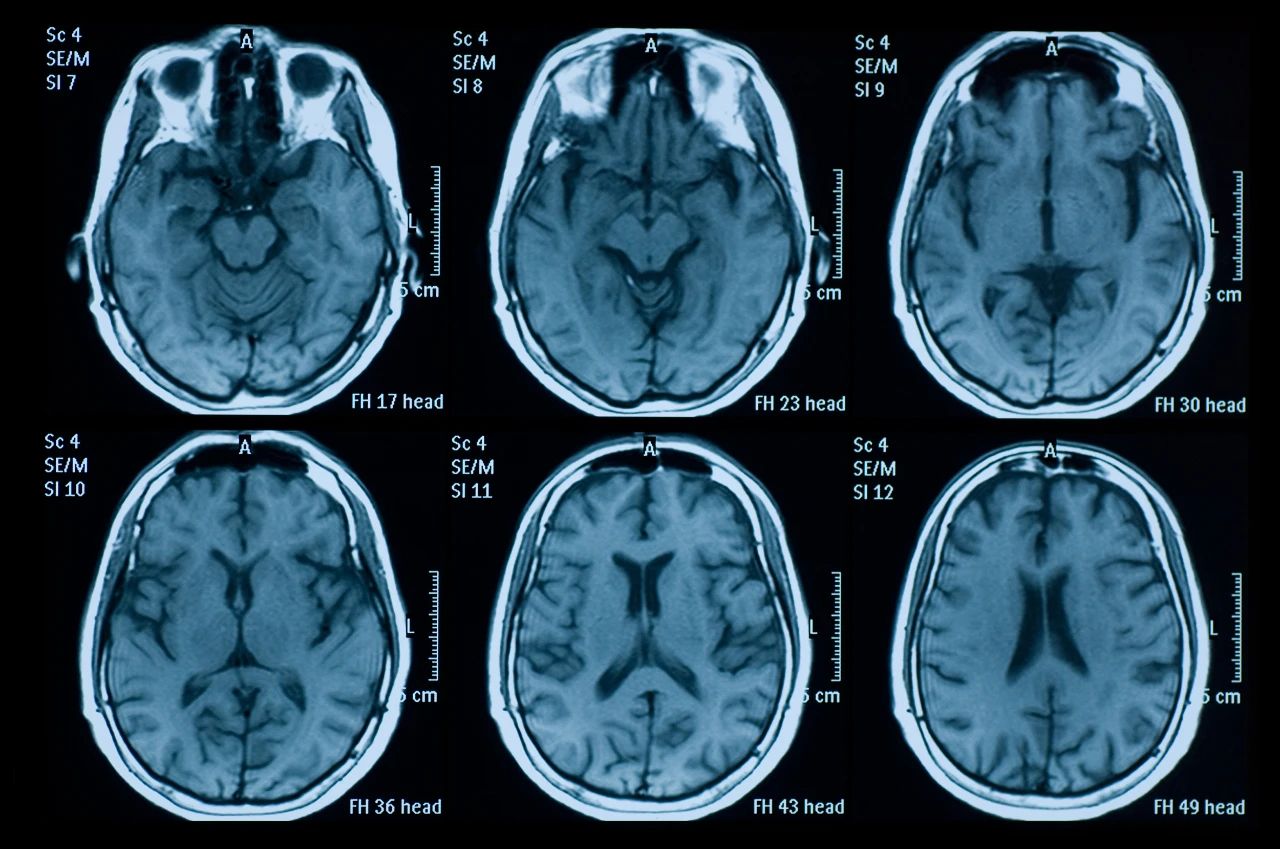

什么是創(chuàng)傷性腦損傷?

頭部受傷是頭部受到撞擊。它可能是輕微的,導(dǎo)致小腫塊或瘀傷,也可能更嚴(yán)重,導(dǎo)致腦損傷,如腦震蕩或腦出血。

即使您看不到頭部受傷也可能很嚴(yán)重。它們可能導(dǎo)致永久性殘疾或損傷,甚至死亡。更嚴(yán)重的頭部受傷總是需要去看醫(yī)生。